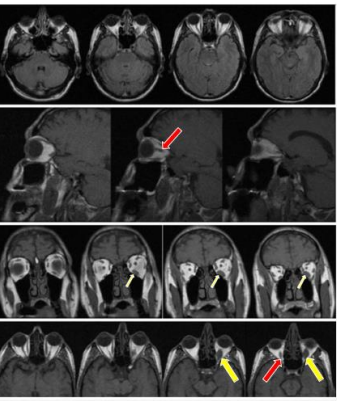

Figure 2: Magnetic resonance imaging (MRI) - Line 1: axial section in the Flair sequence

Line 2: sagittal section, in T1 sequence. Line 3: coronal section, in T1 sequence. Line 4: axial section, in T1 sequence. Showing typical findings of Graves' orbitopathy with marked fusiform thickening in the fascicles of the bellies of the extrinsic muscles of the right and left orbits (red arrow), severely in the belly of the inferior rectus muscle on the left (yellow arrow).